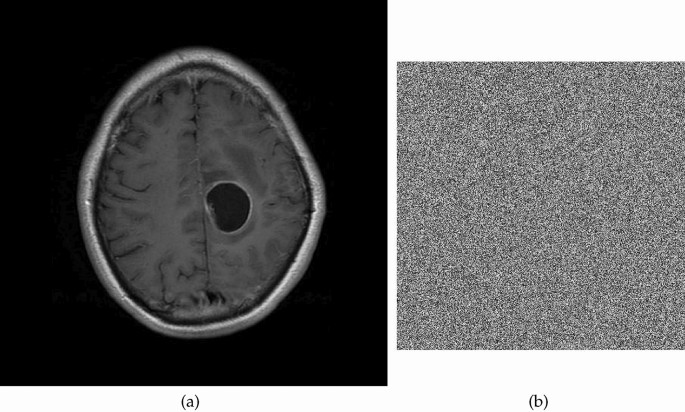

Image encryption

The utilization of the proposed S-box in the realm of encrypting medical images demonstrates a potential avenue for enhancing data security and privacy within healthcare systems. Strong protection against unauthorized access and online threats is required due to the delicate nature of medical images, which frequently contain sensitive patient information. When the innovative S-box is incorporated into encryption techniques, it offers a way to enhance the security of these priceless medical assets. The S-box enables the development of complicated encryption algorithms that thwart adversaries’ attempts to undermine the security of medical images by increasing the non-linearity and confusion aspects of encryption methods. In the constantly changing world of healthcare technology and information security, this novel technique has the potential to significantly protect patient privacy and guarantee the accuracy of medical data. We employed the CBC mode of AES to encrypt plain images with the proposed S-box. The corresponding images are displayed in Figs. 1, 2, 3, 4, 5, 6, 7 and 8. The Fig. 9 depicts the strength against salt and pepper noise with different intensity levels and Table 3 discusses the different tests for an image encryption.

Plain and cipher MRI image.

Histogram of plain and cipher MRI image.